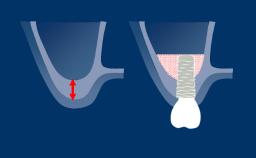

The use of implant-supported dental prostheses to replace missing teeth has resulted in a renewed focus on extraction techniques, particularly in the esthetic zone.

Removing the tooth without damaging the alveolar socket can facilitate post-operative healing, ridge preservation techniques and subsequent implant placement.

This module will describe the techniques to remove a hopeless tooth with implant placement in mind.